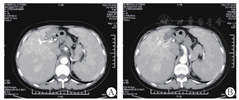

上腹部CT增强扫描:遗传性出血性毛细血管扩张症(肝动脉-门静脉瘘),肝硬化,脾大,门静脉高压,门静脉右支局限性瘤样扩张,少量腹腔积液(图2)。

该患者查血常规提示三系减少,PⅢP N-P、CIV、HA均升高超过正常值的2倍。上腹部CT平扫:肝硬化征象;脾大,胃底、脾门血管增粗,少量腹腔积液。上腹部CT增强:肝硬化,脾大,门静脉高压,门静脉右支局限性瘤样扩张,少量腹腔积液。明确诊断为肝硬化。病因上患者病毒标志物阴性、自身免疫性肝病相关抗体阴性,无饮酒史、用药史、化学毒物接触史、寄生虫感染史。结合该患者上腹部CT增强示遗传性出血性毛细血管扩张症(肝动脉-门静脉瘘),门静脉右支局限性瘤样扩张。下腔静脉造影及肝静脉造影术:门静脉右支局限性瘤样扩张。故该患者由于HHT累及肝脏形成肝动脉-门静脉分流,可引起肝淤血,长期肝脏淤血最终可发展为淤血性肝硬化。患者入院查肝生物化学指标:GGT 119.00 U/L,ALP 142.00 U/L。胆道系统的血液由肝动脉供应,动静脉短路后可导致胆道系统血液灌注不足,肝内或肝外胆管缺血性坏死[3]。该患者出现肝动脉-门静脉分流,故GGT、ALP出现升高。